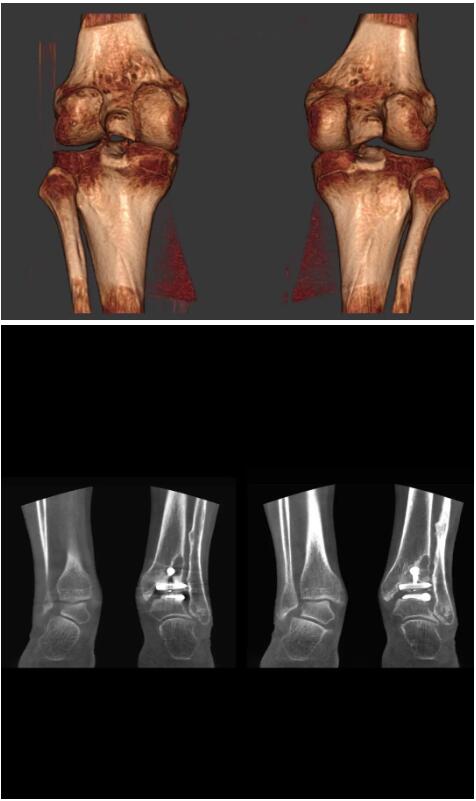

以上介紹的CT均來自國外同一家公司,這些CT均配置了可視化軟件,可以進(jìn)行切片、3D重建以及大型CT附帶的所有典型的操作功能。

以下是這些“特立獨(dú)行”的CT所拍出來的圖像: